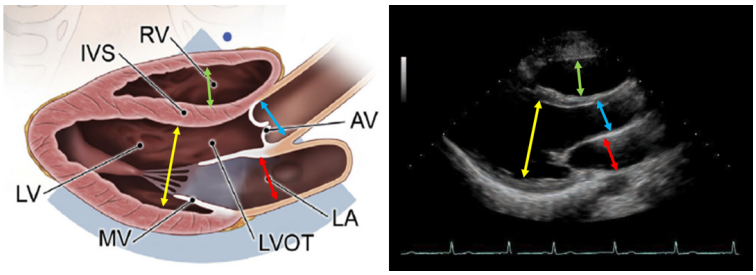

在胸骨旁长轴(PLAX)切面,我们可以测量左心室、右心室舒张末前后内径和主动脉根部的内径及左心房内径。左心室等容舒张期进行测量,男性左心室心腔大小为4.2~5.9 cm,女性为3.9~5.3 cm。操作示意图见图3。

图片

图3. PLAX下测量左心室舒张末前后径(黄色)、右心室舒张末前后径(绿色)、左心房内径(红色)、主动脉根部内径(蓝色)的示意图